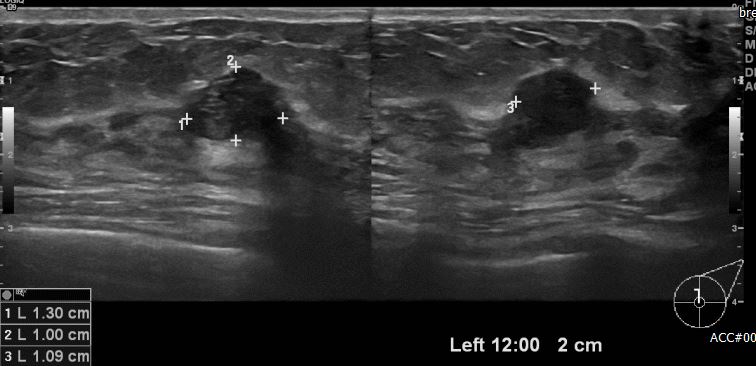

상기환자 좌측유방에 만져지는 혹있어 내원하신 40대 여자환자분으로 좌측 3시방향으로

의심스런 결절있어 중심핵생검 실시하여 제자리암 진단되셨습니다.